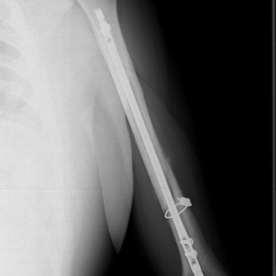

Röntgenbilder